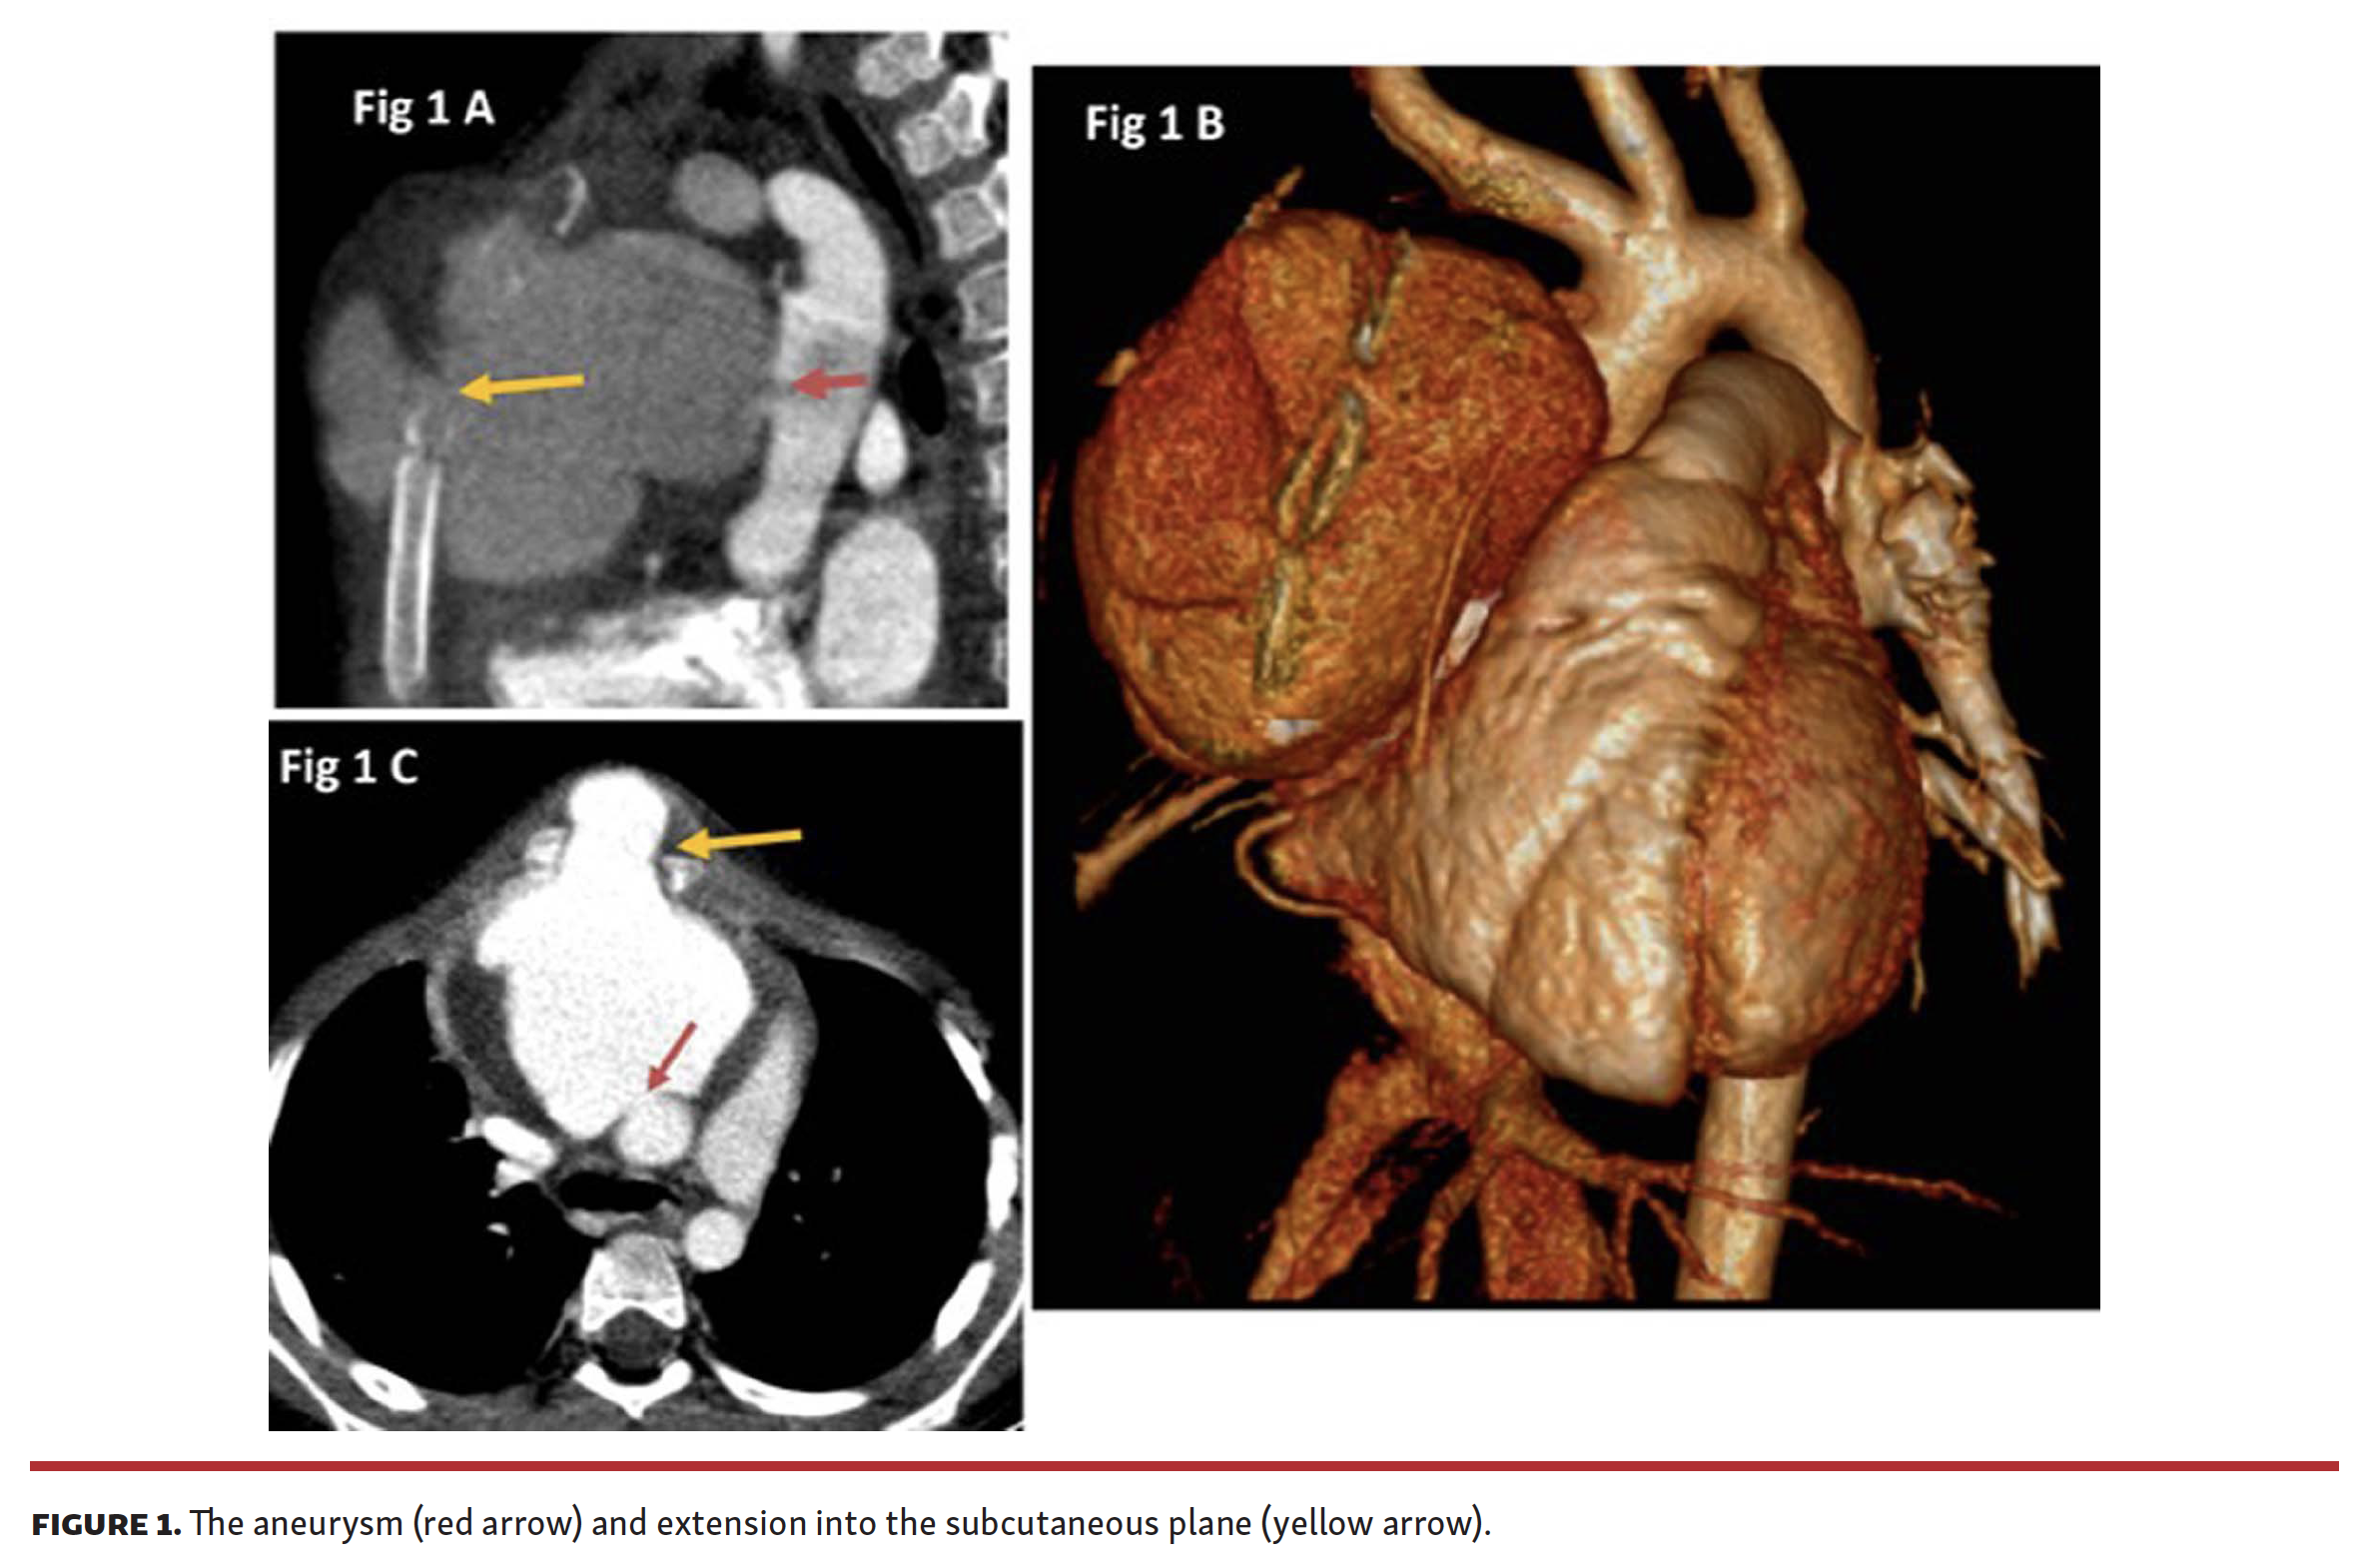

A 7-year-old boy was referred with diagnosis of a large aortic pseudoaneurysm 2 weeks after surgical closure of perimembranous ventricular septal defect with blood culture growing coagulase-negative staphylococcus (Video 1). Contrast-enhanced cardiac computed tomography showed an 8 x 7 cm aortic aneurysm arising from the anterior part of the ascending aorta at the site of aortic cannulation, which was extending into the subcutaneous plane of the chest through the median sternotomy (Figure 1). Due to the subcutaneous extension and risk of spontaneous rupture, we decided that a percutaneous strategy was a safer alternative to surgery.